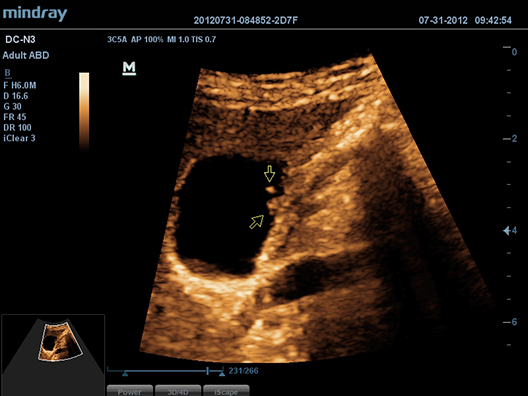

iScapeTM

–Ф–∞–µ—В –њ–Њ–ї–љ—Л–є –Є —А–∞—Б—И–Є—А–µ–љ–љ—Л–є –Њ–±–Ј–Њ—А –∞–љ–∞—В–Њ–Љ–Є—З–µ—Б–Ї–Є—Е —Б—В—А—Г–Ї—В—Г—А –њ–Њ—Б—А–µ–і—Б—В–≤–Њ–Љ –њ–∞–љ–Њ—А–∞–Љ–љ–Њ–є –≤–Є–Ј—Г–∞–ї–Є–Ј–∞—Ж–Є–Є, –≤ —Б–Њ—З–µ—В–∞–љ–Є–Є —Б –Є–љ–і–Є–Ї–∞—В–Њ—А–Њ–Љ —Б–Ї–Њ—А–Њ—Б—В–Є –Є —Д—Г–љ–Ї—Ж–Є–µ–є –њ—А—П–Љ–Њ–≥–Њ / –Њ–±—А–∞—В–љ–Њ–≥–Њ —Б–Ї–∞–љ–Є—А–Њ–≤–∞–љ–Є—П, –і–µ–ї–∞—П –њ—А–Њ—Ж–µ—Б—Б –±–Њ–ї–µ–µ –ї–µ–≥–Ї–Є–Љ, –њ–Њ—Б–ї–µ–і–Њ–≤–∞—В–µ–ї—М–љ—Л–Љ –Є —Г–њ—А–∞–≤–ї—П–µ–Љ—Л–Љ.

ExFOV

–Т –Т–∞—И–µ–Љ —А–∞—Б–њ–Њ—А—П–ґ–µ–љ–Є–Є –Њ–Ї–∞–ґ–µ—В—Б—П —Б–∞–Љ–∞—П –њ–Њ–ї–љ–∞—П –і–Є–∞–≥–љ–Њ—Б—В–Є—З–µ—Б–Ї–∞—П –Є–љ—Д–Њ—А–Љ–∞—Ж–Є—П –±–ї–∞–≥–Њ–і–∞—А—П –і–µ—В–∞–ї–Є–Ј–Є—А–Њ–≤–∞–љ–љ–Њ–є –≤–Є–Ј—Г–∞–ї–Є–Ј–∞—Ж–Є–Є –∞–љ–∞—В–Њ–Љ–Є—З–µ—Б–Ї–Є—Е —Б—В—А—Г–Ї—В—Г—А –љ–∞ –≤—Б–µ—Е –Ї–Њ–љ–≤–µ–Ї—Б–љ—Л—Е –Є –ї–Є–љ–µ–є–љ—Л—Е –і–∞—В—З–Є–Ї–∞—Е.